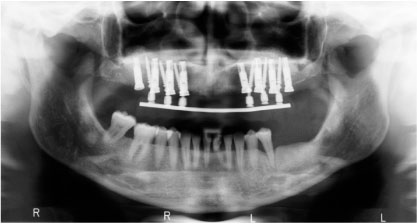

Επίσης, πλέον μία πολύ συχνή επέμβαση είναι η τοποθέτηση οστικού μοσχεύματος στα ιγμόρια άντρα για δημιουργία οστικού όγκου, με σκοπό την τοποθέτηση οδοντικών εμφυτευμάτων στην άνω γνάθο.

Αποτελεί και αυτή επέμβαση ρουτίνας για τους Στοματικούς και Γναθοπροσωπικούς Χειριουργούς, με αποτέλεσμα που αγγίζει σχεδόν πάντα το άριστο. Και εδώ το πιό συχνό αίτιο αποτυχίας, είναι το ίδιο όπως αναφέρθηκε πρωτύτερα για τους φρονιμίτες. Είναι πλέον γνωστό σε όλους ότι τα οδοντικά εμφυτεύματα συμβάλλουν στην αποκατάσταση της λειτουργίας της μάσησης, της κατάλληλης σύγκλισης και της διατήρησης  του οδοντικού φραγμο

Κάποιοι ασθενείς δεν προτιμούν τις κινητές οδοντοστοιχίες ως προσθετική αποκατάσταση, καθώς και άτομα μικρής ηλικίας με απώλεια δοντιών, η επιλογή των οδοντικών εμφυτευμάτων είναι η προτιμότερη λύση. Αλλά ακόμα και στους ασθενείς που έχουν προσαρμοστεί με τις ολικές οδοντοστοιχίες, αλλά δυσανασχετούν με την κινητικότητα αυτών πάλι τα οδοντικά εμφυτεύματα δίνουν καθοριστική λύση.